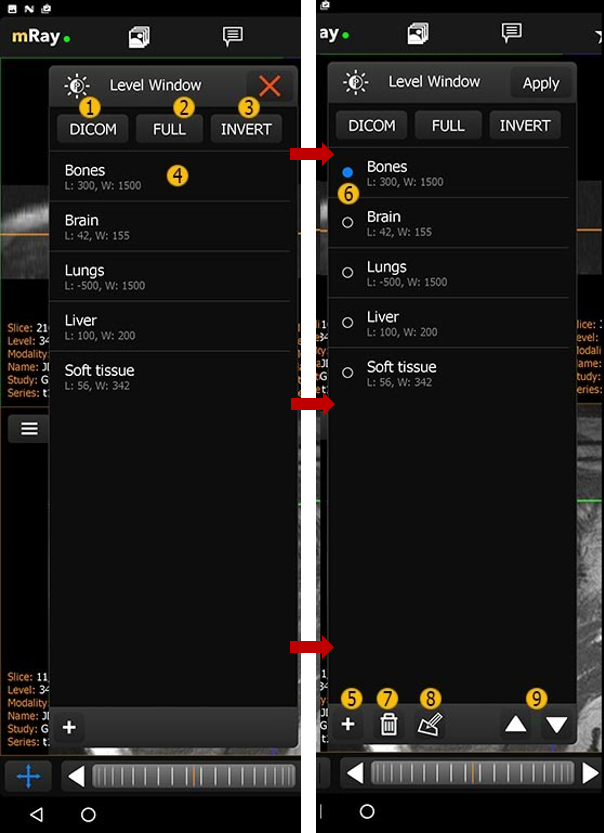

10.6. Level-Window presets

mRay allows you to create presets for the Level-Window tool. These can be selected from the Level-Window menu (on the right Level-Window presets). Please note: These presets are saved to the device and are not synced to other devices.

-

DICOM: Sets the level window to the settings set in the DICOM tags.

-

FULL: Set the level window to the full spectrum of grayscale values.

-

INVERT: Like full, but inverted.

-

Level-window-preset

-

Tap: Sets the level window for the active view.

-

Double Tap: Sets the level-window for the active view and closes the presets window.

-

Hold: Selection of Preset(s)

-

-

Creates a new preset.

-

Select one or more presets.

-

Delete the selected preset.

-

Edit the selected preset (Edit Level-Window preset).

-

Move preset up/down.